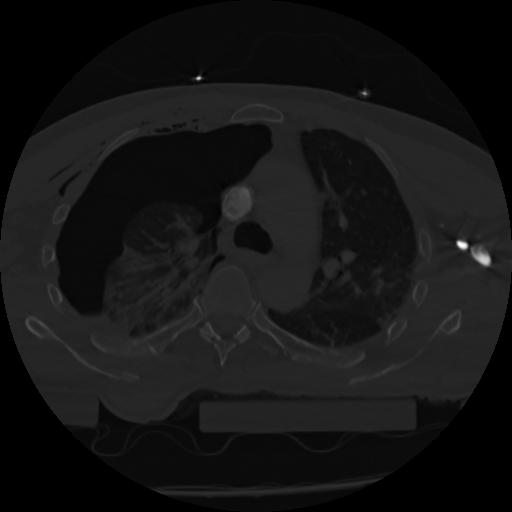

22 ANGIO,CE,Vol,0.5,ANGIO,,